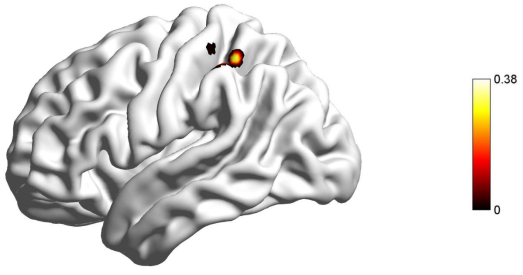

近日,必赢776net必赢776net冯廷勇教授团队在国际著名学术期刊《Behavioral and Brain Functions》(中科院分区SCI一区,IF = 5.1)上发表了名为“The vmPFC-IPL functional connectivity as the neural basis of future self-continuity impacted procrastination: the mediating role of anticipated positive outcomes”的学术论文。该研究基于预期想象的2(指向性:任务过程VS.任务结果)×2(情绪效价:正性VS.负性)模型(Yang & Feng, 2021),采用自由建构范式,收集被试的预期想象想法,并结合基于体素的形态学分析(VBM)和静息态功能连接(RSFC)两种多模态分析方法,深入探究了未来自我连续性影响拖延的神经基础。该研究发现:(1)行为结果表明,未来自我连续性与拖延行为呈负相关关系(见图1);(2)VBM结果发现,未来自我连续性与右侧腹内侧前额叶(right ventromedial prefrontal cortex,RvmPFC)的灰质体积呈正相关关系(见图2);(3)RSFC分析揭示,右侧腹内侧前额叶与左侧顶下小叶(left inferior parietal lobule, LIPL)之间的功能连接(RvmPFC-LIPL)强度与未来自我连续性呈正相关关系(见图3);(4)中介分析发现,预期想象正性结果在未来自我连续性的功能连接(RvmPFC-LIPL)对拖延行为的影响中起到了完全中介的作用(见图4)。基于拖延的时间决策模型(Zhang & Feng, 2020),这些结果说明,未来连续性主要通过预期想象增加正性结果价值,进而减少了拖延行为。本研究从认知神经角度系统地解答了“未来自我连续性通过什么心理过程减少拖延行为”,也为拖延的干预提供了新的视角和理论依据。

图3 右侧腹内侧前额叶与左侧顶下小叶的功能连接与未来自我连续性呈显著正相关